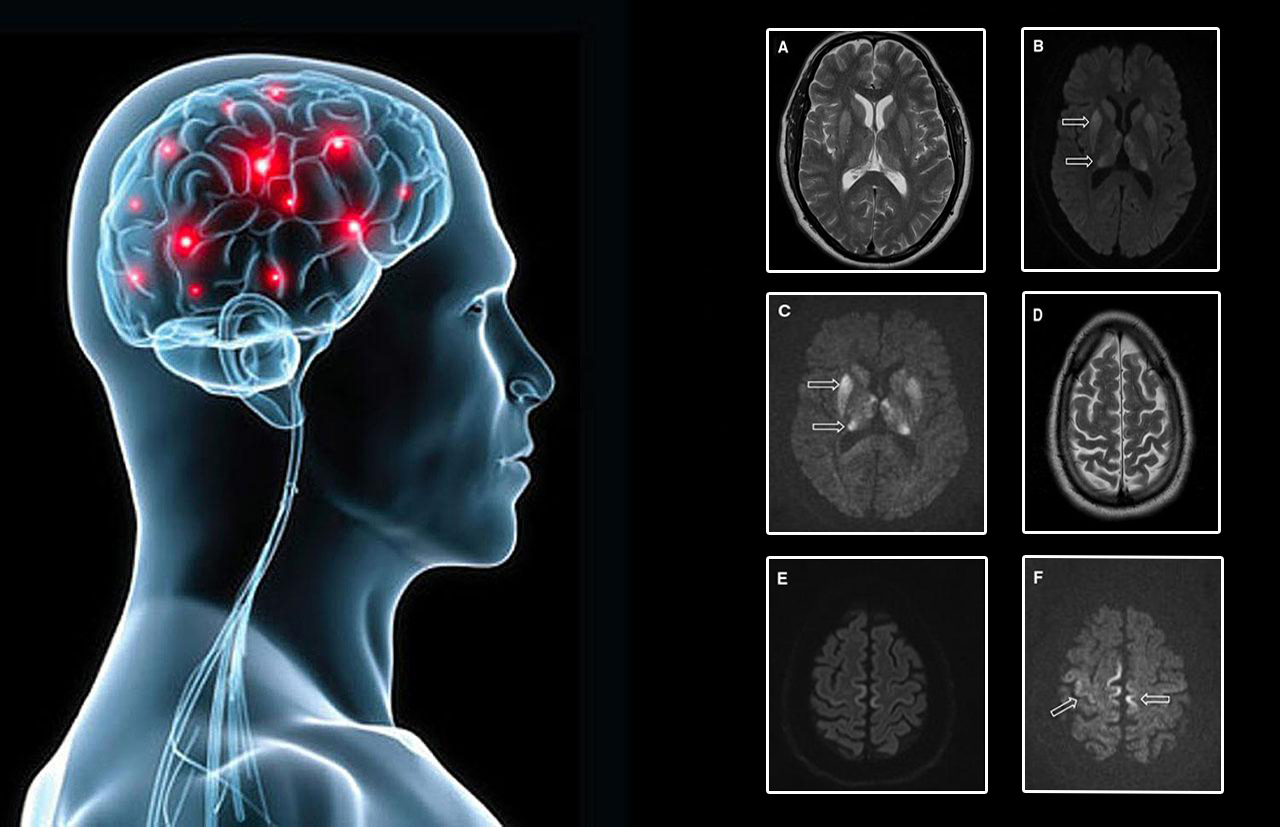

• Mozek pacienta s Creutzfeldtovou–Jakobovou chorobou. Šipky ukazují místa zasažená prionem.